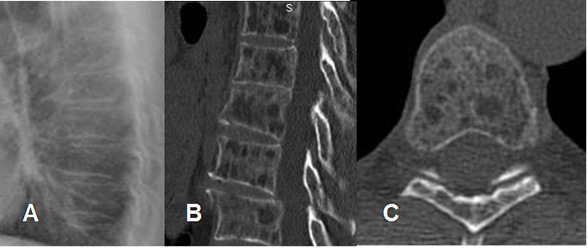

Fig 230. Micrometástasis.

A: Rx lateral. No se encuentran alteraciones.

B: TAC reconstrucción sagital y C: TAC axial. Múltiples lesiones líticas vertebrales, por micrometástasis secundaria a infiltración leucémica.